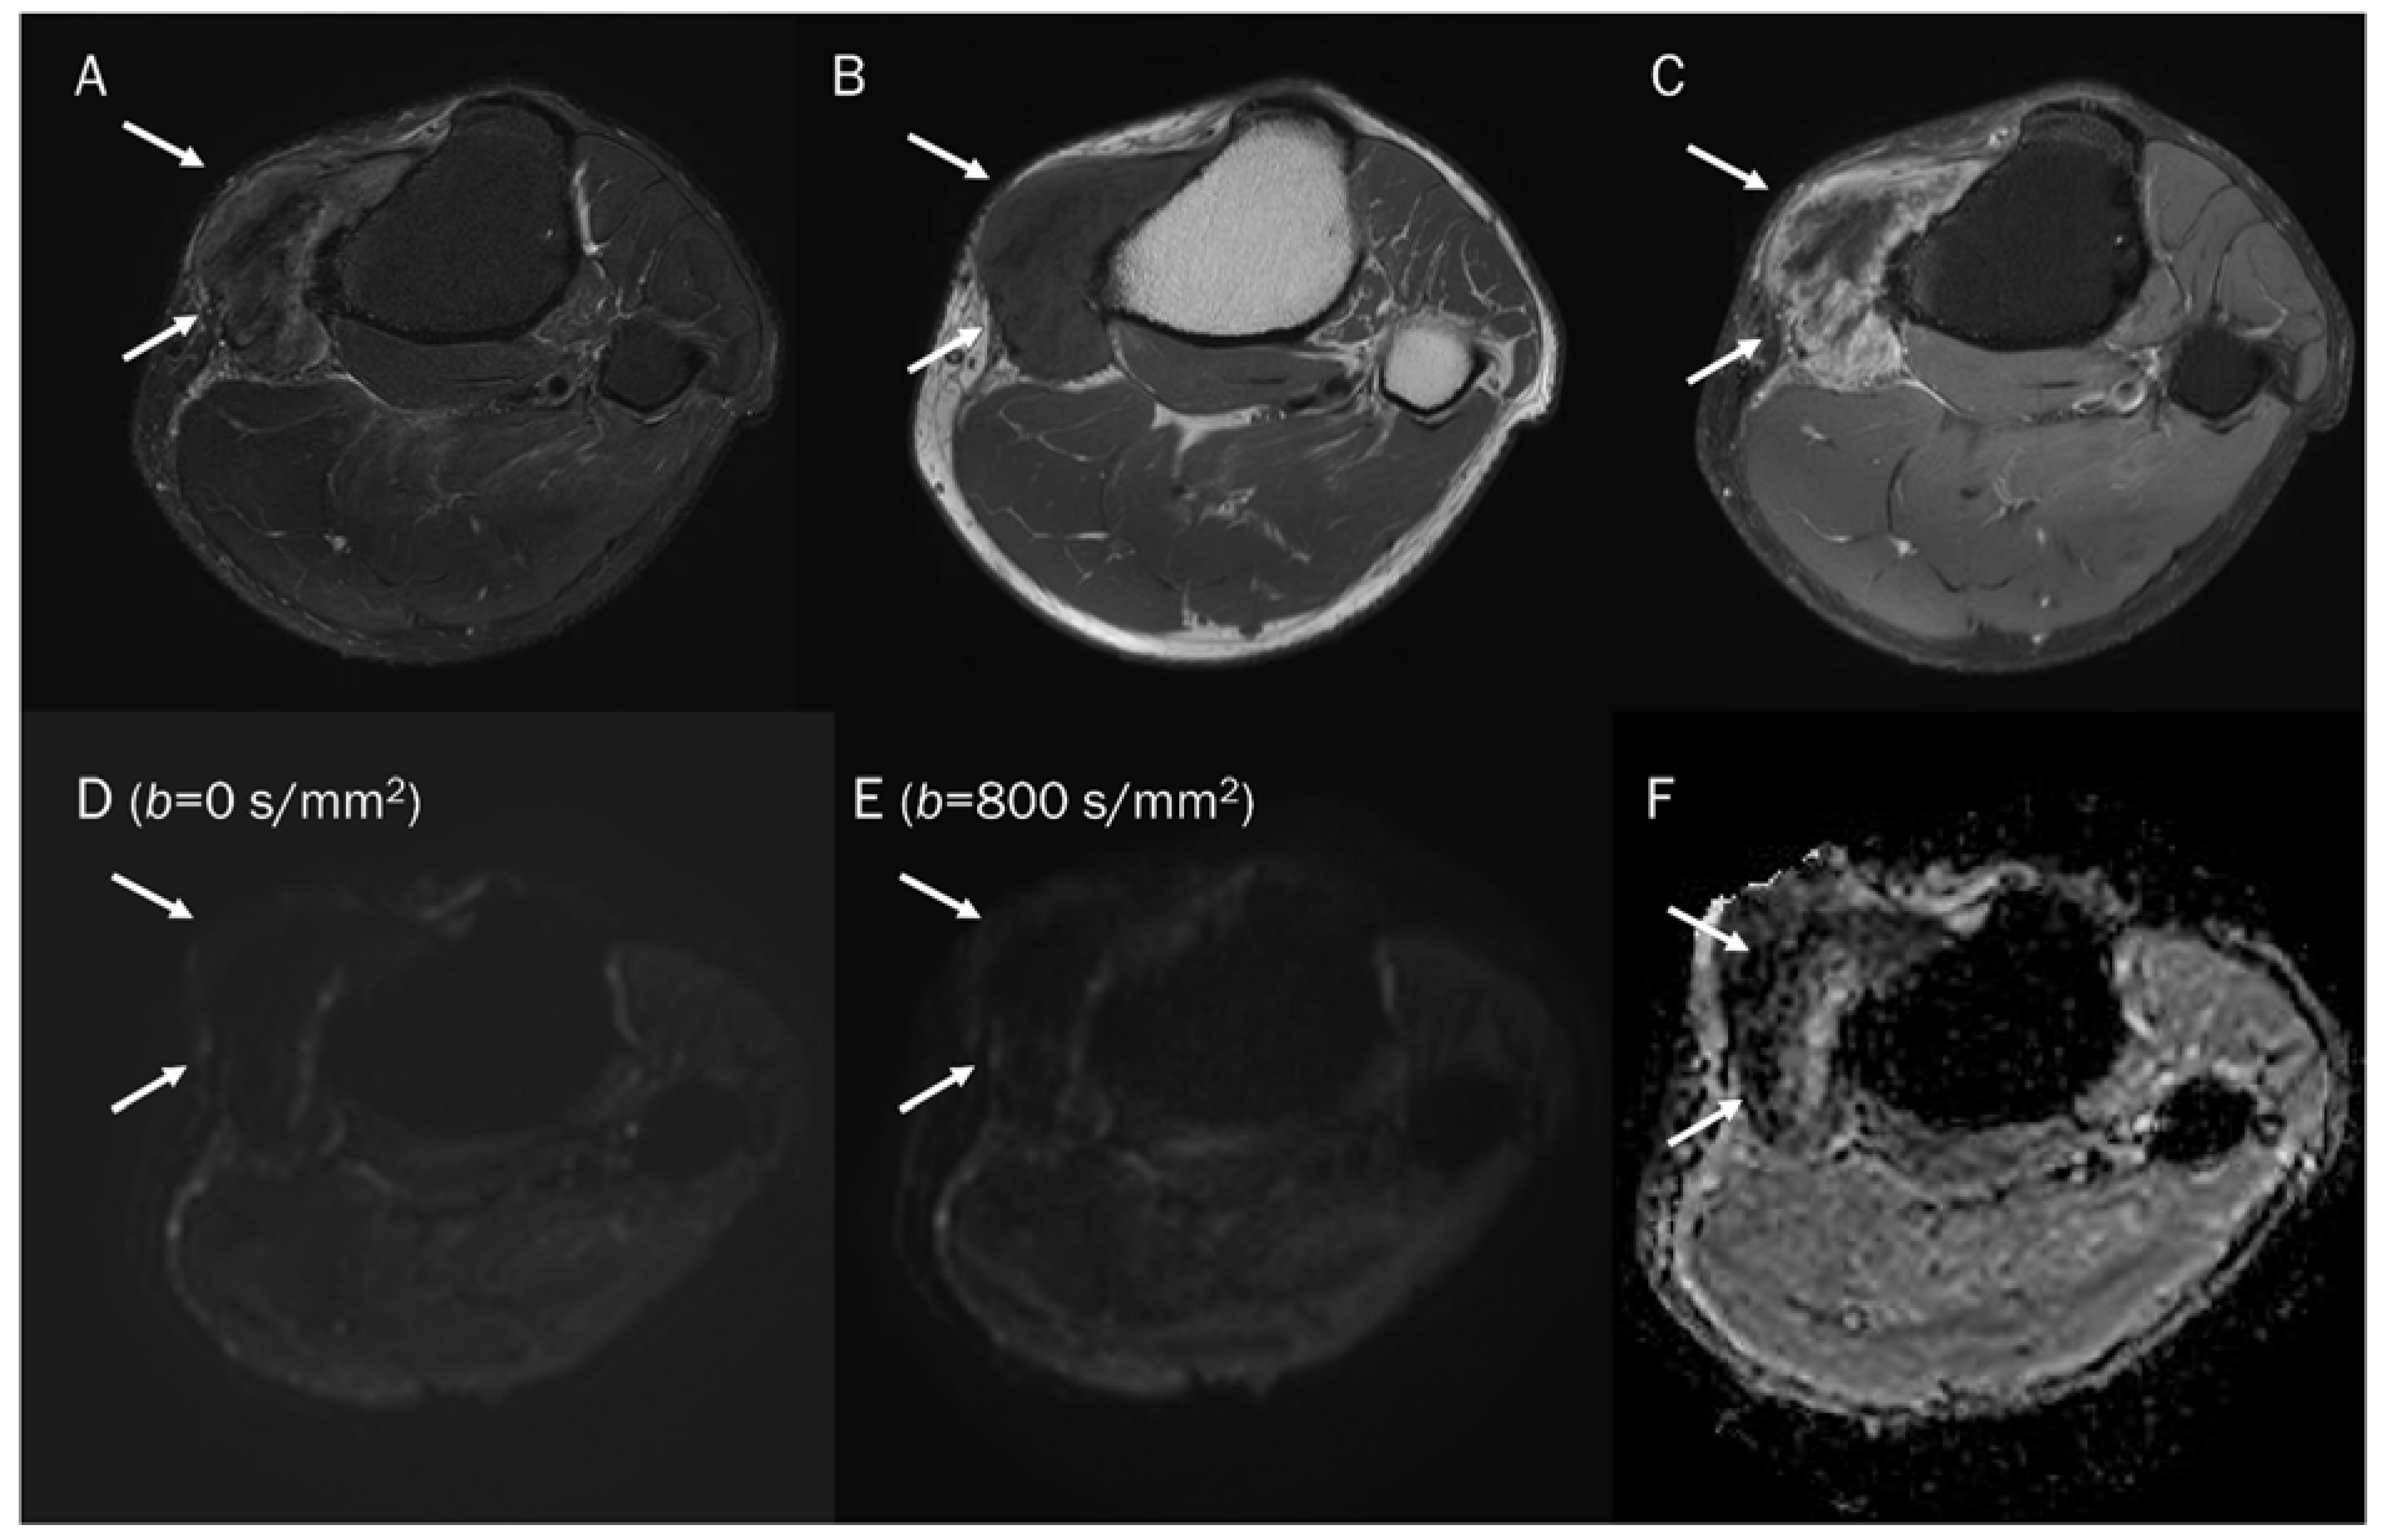

5.1. T2 Shine-through Effect

5.2. T2 Black-out Effect

7.1. Cyst

7.2. Hematoma